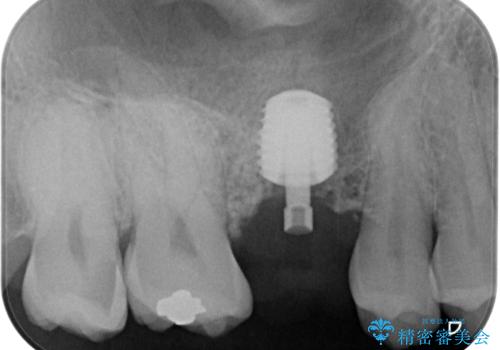

インプラント処置は、抜歯即時埋入を行い、十分な安定性が確認できたため、当日仮歯を装着しました。

インプラントが生着するのを待っている間に反対側の根管治療を行い、左右同時に補綴治療を行いました。

補綴治療後3ヶ月での経過は良好で、引き続き経過観察を行っていきます。